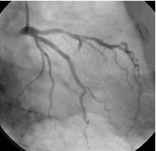

同じ患者様のカテーテル検査の写真です。(CTと同じ所に狭い部分があります) -